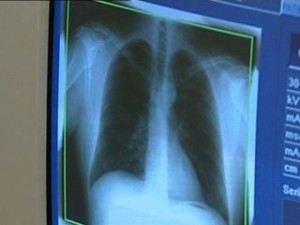

Tájékoztatjuk a község lakosságát, hogy a 2014-es évben a Jósa András Oktató Kórház szervezésében ismét lesz Nyírkarászon ingyenes tüdőszűrő vizsgálat.

A tüdőszűrésen való megjelenés betöltött 40 éves kortól AJÁNLOTT és INGYENES!